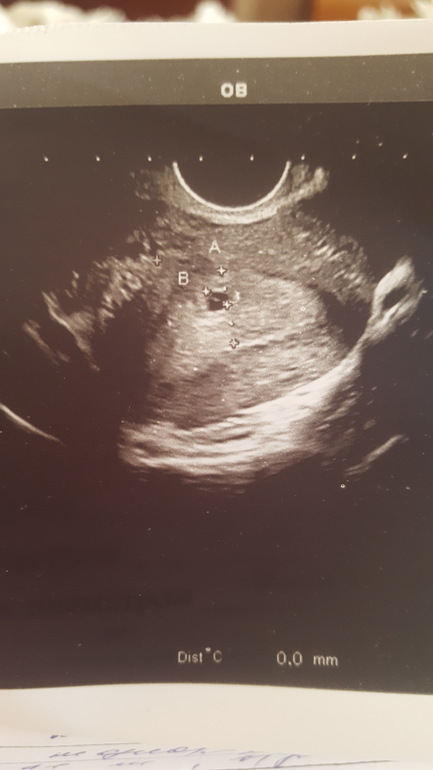

По итогу она повернула ко мне монитор и сказала, что беременность есть, срок маленький, всего лишь 4 недели, размер 4 мм. От переполняющих эмоций даже забыла спросить, эмбриональный это срок или нет. Но, с учетом того, что я сразу сказала, что цикл нерегулярный, я так понимаю, что это именно эмбриональный, а акушерский получается 6 недель. Радости просто нет предела. Безумно боялась, что будет внематочная. Но все хорошо, будем расти)

Поздравляю 🥳 но это у вас акушерский срок (4 недели), на 6ой неделе уже плодное яйцо намного больше, есть желточный мешочек и эмбрион, и может просматриваться сердцебиение)

На 6 акушерской неделе плодное яйцо 11-18мм. Почитайте по ссылке ниже) скорее всего Вам приложение говорит размер ктр, а не плодного яйца)

У меня в 5 Нед 5 дней уже был эмбрион 2.7мм ) у вас ещё совсем кроха 😇 только только начинает расти)